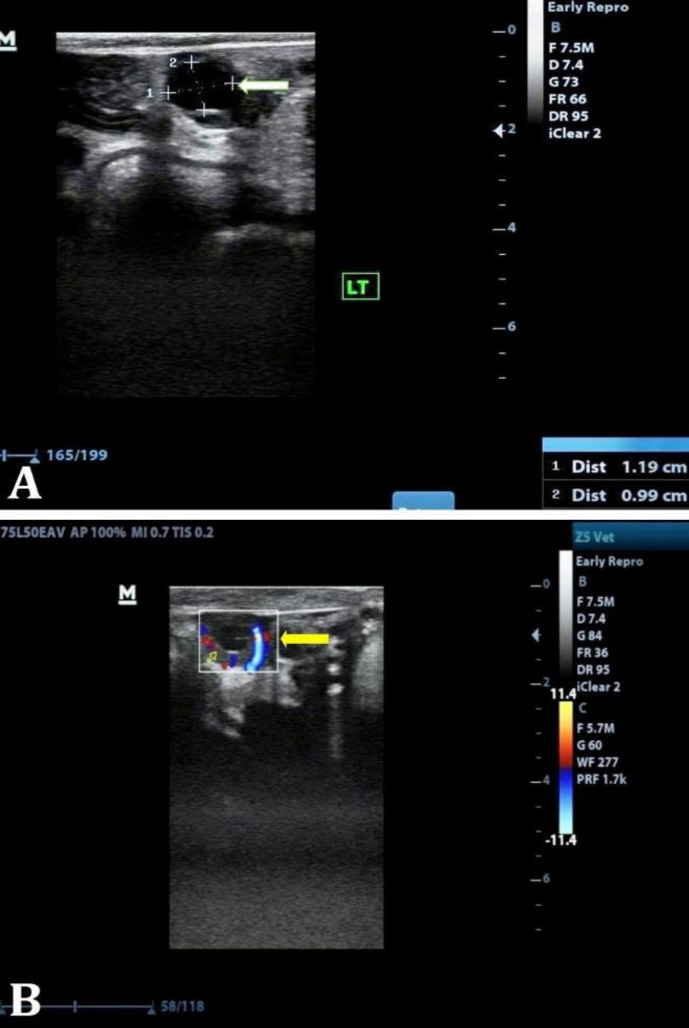

本研究旨在评估健康或患病子宫的周期性奶牛(N = 130)在发情至排卵期间的血清孕酮(P4)浓度和子宫血流动力学。在发情期,85 头奶牛被诊断为临床子宫内膜炎(CE;n = 44)和亚临床子宫内膜炎(SCE;n = 41);而作为对照的 45 头奶牛即无子宫内膜炎(NE;n = 45)被纳入研究。在发情开始后 12 - 14 小时和 40 小时进行血清孕酮测定,并对两侧子宫中动脉进行多普勒超声检查,以了解子宫血流动力学和排卵情况。CE和SCE奶牛在发情后12-14小时的血清孕酮浓度明显较高。发情开始后 12 - 14 小时,P4 临界值≥ 0.48 ng mL-1 ,超过此临界值,22.72% 的 CE、26.82% 的 SCE 和仅 8.88% 的 NE 奶牛在发情开始后 36 - 40 小时内未排卵。在多普勒指数中,搏动指数和阻力指数明显较高;而容积指数和速度指数则明显较低。在确诊为CE和SCE的奶牛中,基底上P4浓度、发情时流向子宫的血流速度和血流体积较高,对排卵持续时间有负面影响。

The present research was carried out to assess the serum progesterone (P4) concentration and uterine hemodynamics at estrus till ovulation in cyclic cows (N = 130) with healthy or diseased uterus. At estrus, 85 cows were diagnosed with clinical endometritis (CE; n = 44) and sub-clinical endometritis (SCE; n = 41); whereas, 45 cows being served as control namely no endometritis (NE; n = 45) were included in the study. Serum progesterone estimation at 12 - 14 and 40 hr after the onset of estrus and Doppler sonography of both middle uterine arteries were done to envisage the uterine hemodynamics and ovulation. The serum progesterone concentration was significantly higher at 12 - 14 hr after onset of estrus in CE and SCE cows. At 12 - 14 hr after onset of estrus, a cut-off value of ≥ 0.48 ng mL-1 P4 was obtained, above which 22.72% CE, 26.82% SCE and only 8.88% NE cows failed to ovulate within 36 - 40 hr of estrus onset. Among the Doppler indices, pulsatility and resistance indices were significantly higher; whereas, volume and velocity indices were significantly lower in NE cows. In cows diagnosed with CE and SCE, a higher supra-basal P4 concentration, and velocity and volume of blood flow to uterus at estrus negatively affected the duration to ovulation.